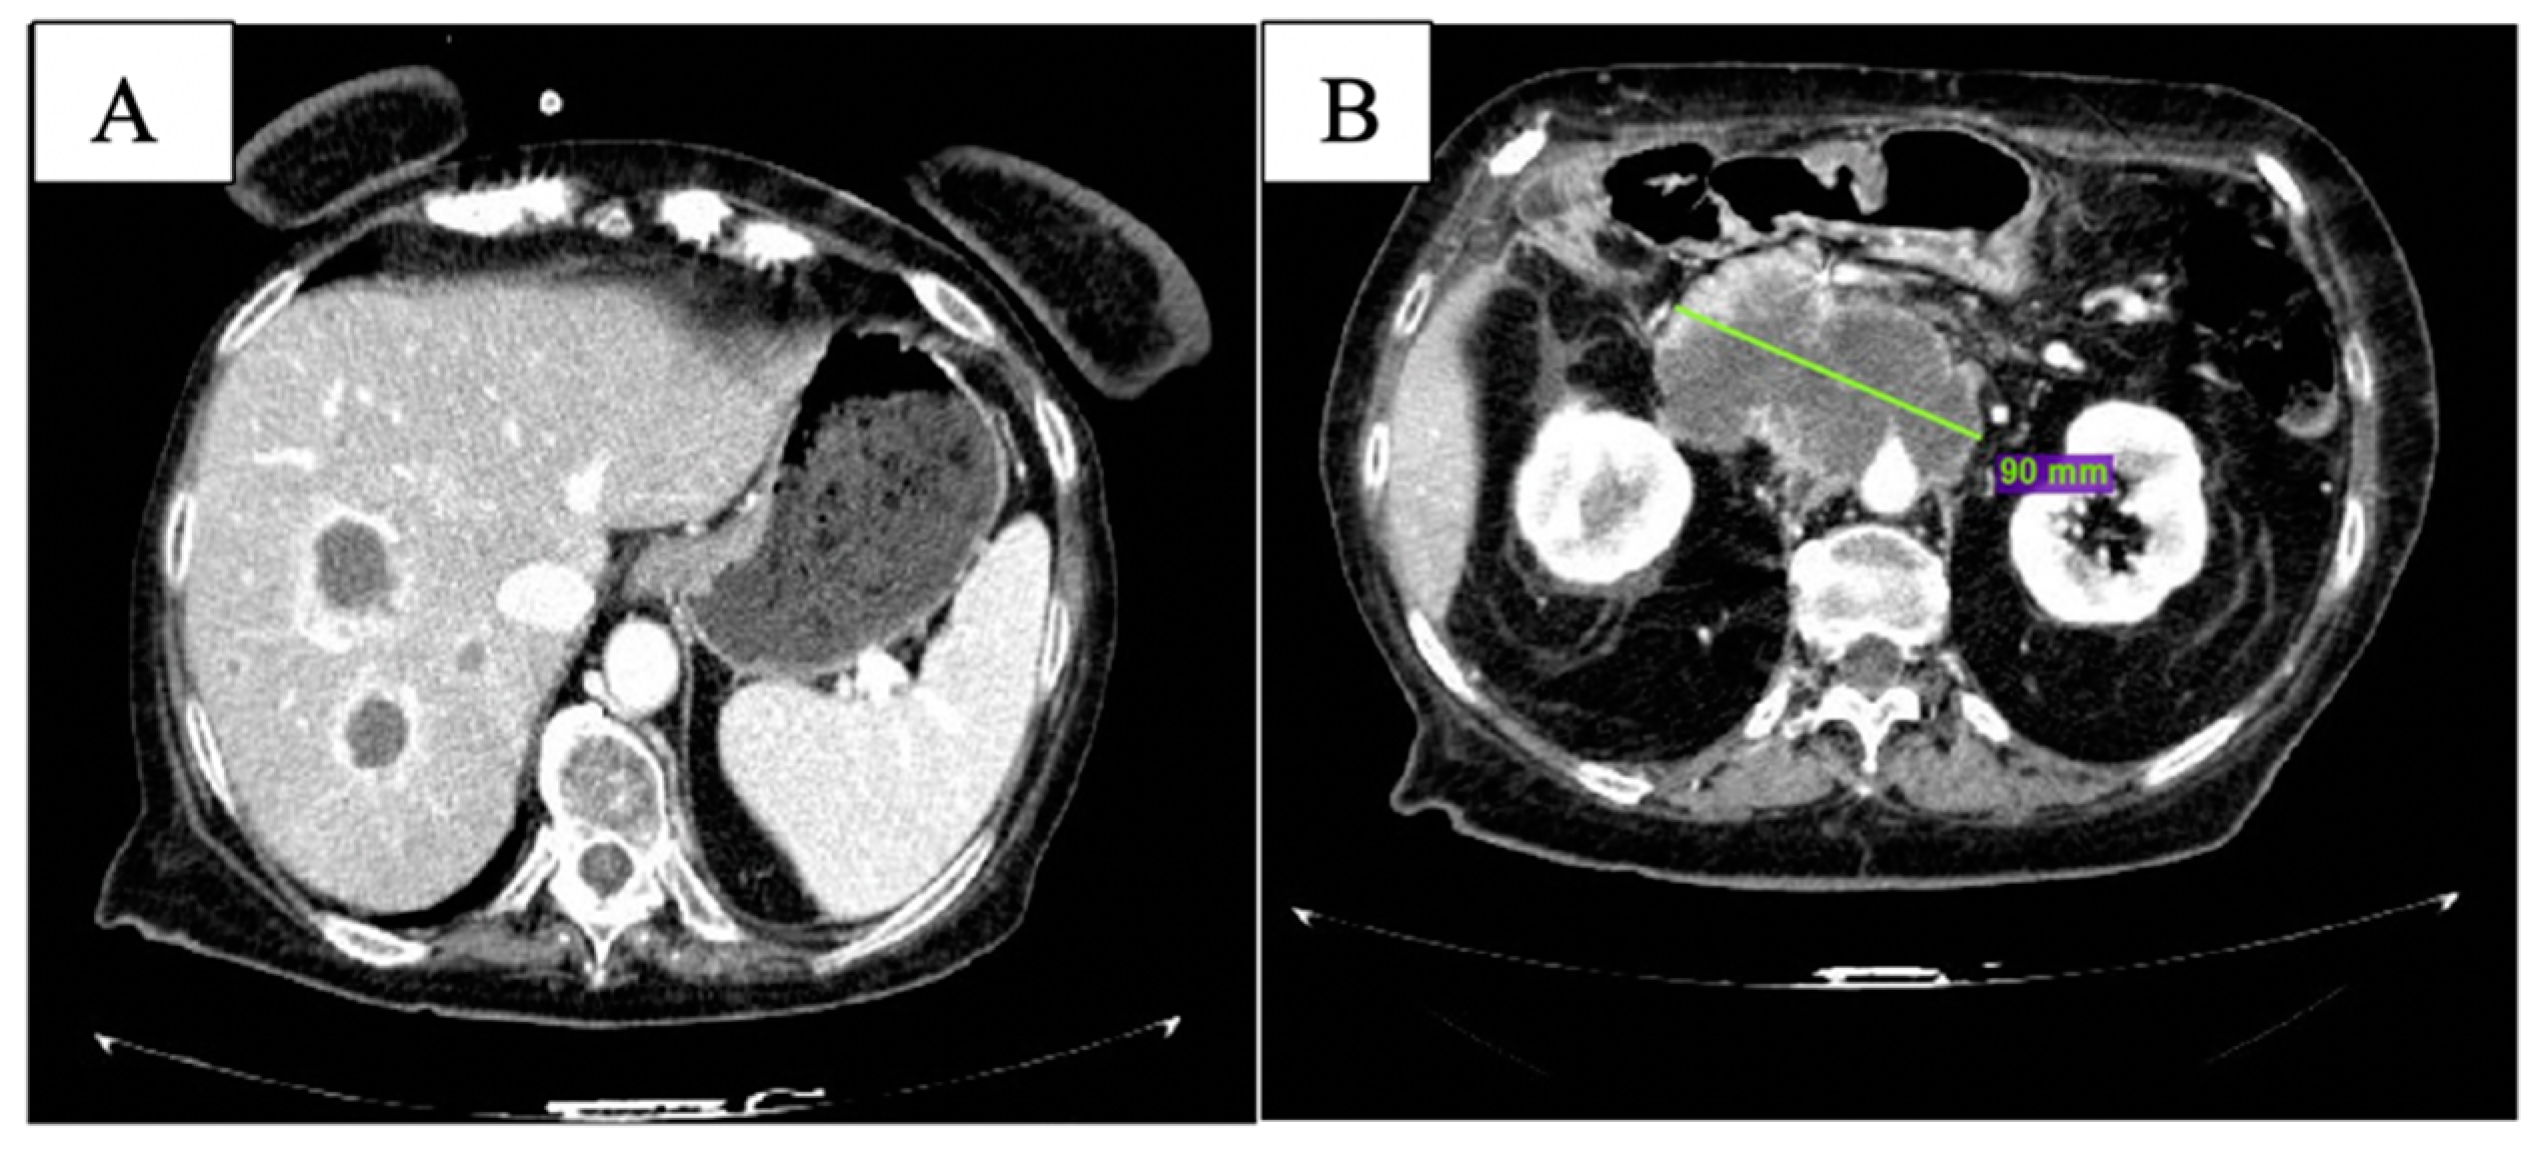

2. Case Description